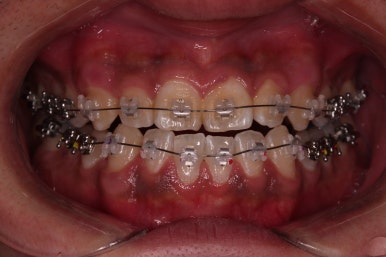

초진 시 입안의 모습입니다.

비교적 고른 편이긴 하나 아랫니가 전반적으로 밀려 나오면서 앞니끼리 부딪혀 있는 양상이고요.

어금니 맞물림도 긴밀하게 톱니바퀴처럼 위아래가 맞물려 있는게 아니라 엉성한 모습이죠.

앵글씨 3급 부정교합이라고 하는데요.